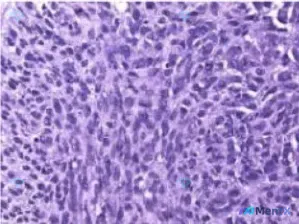

HE染色影像特征

- 背景:高细胞密度,几乎完全被肿瘤细胞占据,间质极少,无明显坏死或显著炎细胞浸润

- 细胞形态:多为梭形、椭圆形或不规则形,胞浆量少

- 核象:核浆比显著增高,核异型性明显(大小不一、形态各异),染色质深染粗颗粒状,部分可见核仁,核分裂象易见

- 排列方式:弥漫片状、杂乱排列,无明确腺管、角化珠等器官样结构